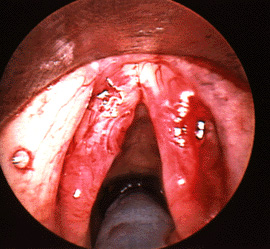

Close up of vocal folds with Reindes edema

The photo to the left shows example of Reinke's edema. (The front of the vocal folds is at the top of the photo.) This disorder is typical in heavy smokers and can produce a low-pitched voice. It is not premalignant, though smokers certainly are at risk for developing laryngeal cancer (as well as heart disease, emphysema, lung cancer and a variety of other problems.) As the edema becomes more gelatinous, it may eventually turn into actual vocal fold polyps.

Close up of post op Reinkes edema

Reinke's edema can be treated surgically by making an incision in the lateral portion of the vocal folds and carefully removing the thick gelatinous fluid in Reinke's space. If there is a lot of excess mucosa (the covering of the vocal fold), this excess mucosa can be trimmed. The photo to the right shows a post-operative view of the folds of the above patient immediately after evacuation of the edema. The goal in this surgery is to preserve the healthy lower layers of the vocal folds and to avoid excessive removal of vocal fold mucosa. This view shows the same patient in the office about three weeks later. This photo was taken through a flexible fiberoptic scope with a different light source, so the colors are slightly different. The folds had already started to vibrate fairly well and the voice was significantly improved. It usually takes 4-6 weeks for all the swelling from the surgery to resolve.

Close up of vocal folds Reinkes edema procedure later post-o

This view shows the same patient in the office about three weeks later. This photo was taken through a flexible fiberoptic scope with a different light source, so the colors are slightly different. The folds had already started to vibrate fairly well and the voice was significantly improved. It usually takes 4-6 weeks for all the swelling from the surgery to resolve.